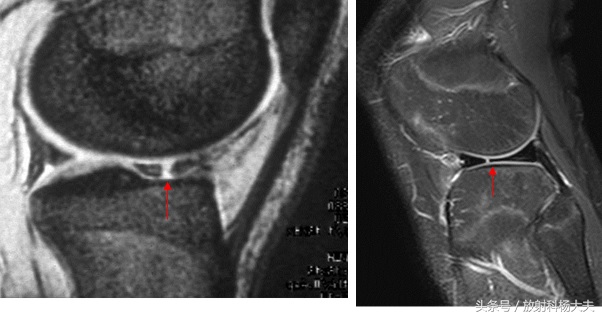

毋庸置疑,最佳的检查手段就是MRI了。用MRI可以检查有无断裂,断裂的程度,以及是否需要手术,手术后的效果等等。包括前后交叉韧带,内外侧副韧带,髌韧带,腘肌腱、股四头肌肌腱等等,膝关节周围的韧带都能在MRI上得到准确的识别和诊断。

半月板断裂

前十字韧带断裂